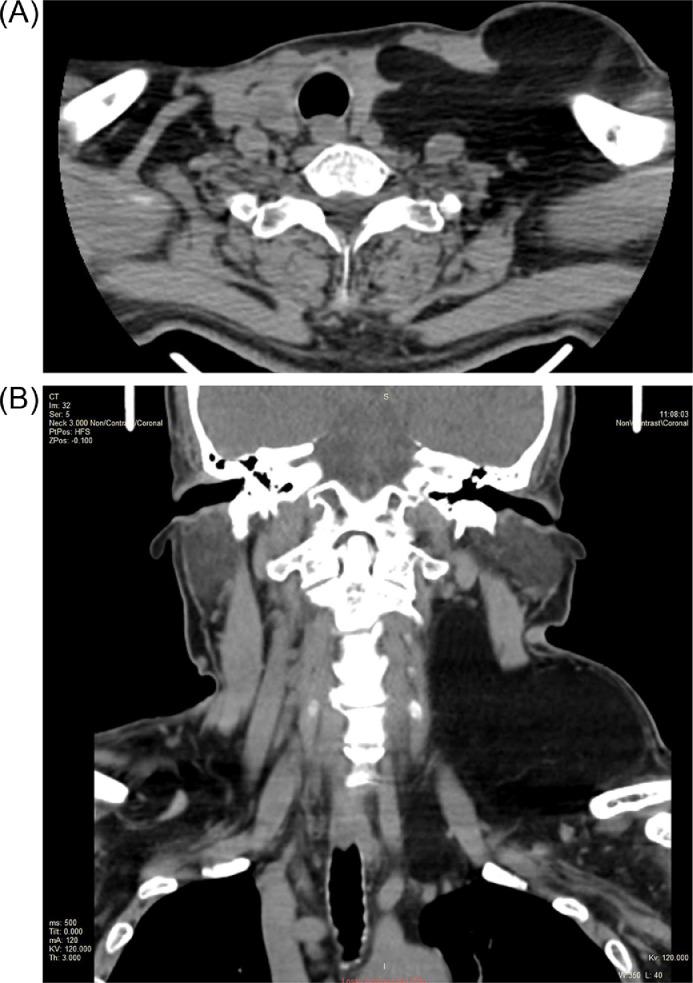

Lipomas are benign and very common subcutaneous tumors of adipose tissue, which may occur anywhere in the body. Lipomas in head and neck regions are extremely rare. A giant neck lipoma is classified as a lesion greater than 10 cm in one dimension or weighing more than 1000 g. In this case report and review of the literature, a 66-year-old male with likely diagnosis of neck lipoma was under 5-year surveillance prior to development of giant neck lipoma. Computed tomography provided critical insight in the extent of neck mass in relation to surrounding structures in assessing possibility of malignancy and in guiding appropriate management.

脂肪瘤是一种常见的良性皮下脂肪组织肿瘤,可发生于身体的任何部位。头颈部脂肪瘤极为罕见。巨大颈部脂肪瘤是指在某一维度上大于10厘米或重量超过1000克的病变。在本病例报告及文献回顾中,一名66岁男性在诊断为颈部脂肪瘤后,在发生巨大颈部脂肪瘤之前接受了5年的监测。计算机断层扫描对于评估颈部肿块相对于周围结构的范围、判断恶性可能性以及指导适当的治疗提供了关键的见解。